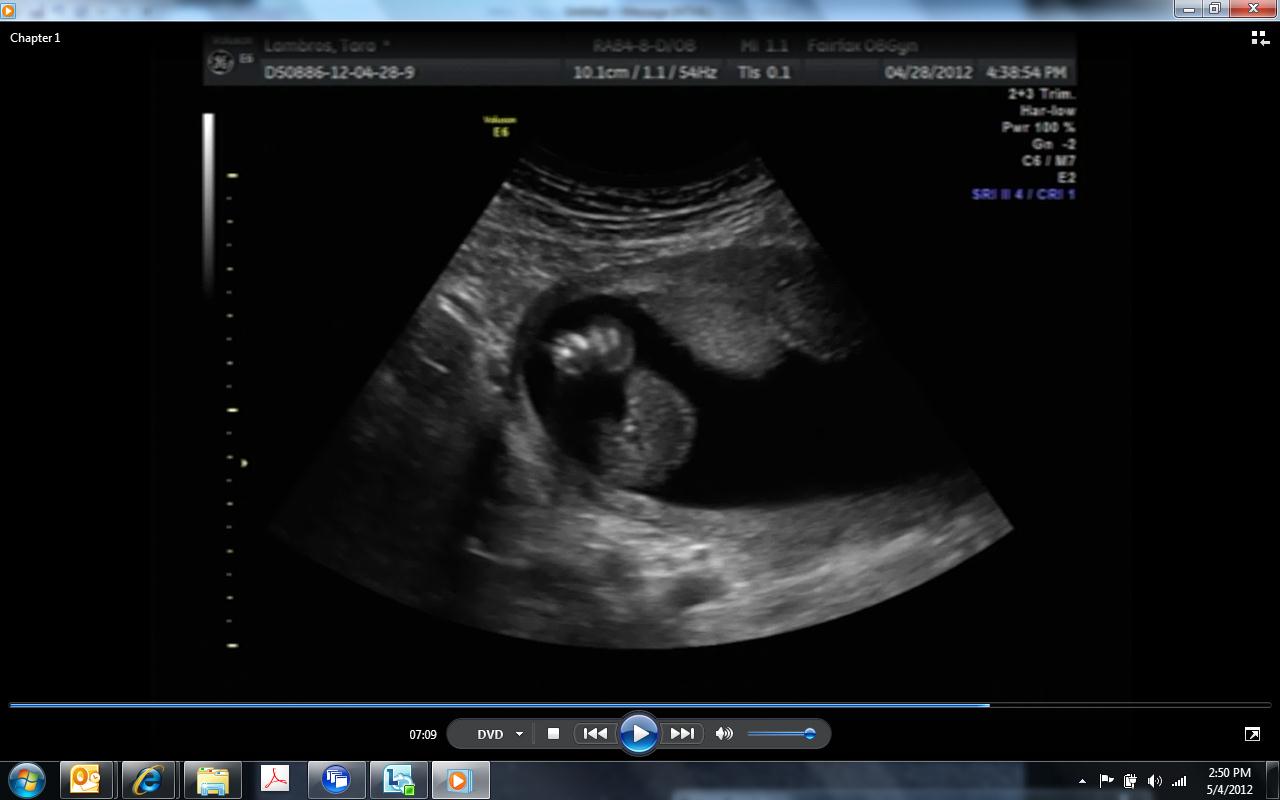

I have no idea what I'm looking at. A few pictures look like a boy and then a few look like a girl. I read that two lines is a boy and three is a girl... looks like 2 to me, but it also looks like a girl to me. LOL... I am no expert. Please help me so I dont have to wait another 3 weeks for confirmation. THANK YOU.

Btw... this is 16 weeks and 3 or 4 days.

The 1st one was not taken straight on and is at a bad angle. If it was a boy then the leg is blocking some of it but if it is a girl then you can't see the 3rd line.